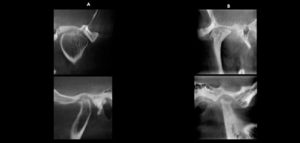

La técnica de Cone Beam se ha transformado en la herramienta primaria de diagnóstico por imágenes más utilizada en el campo del estudio de ATM,